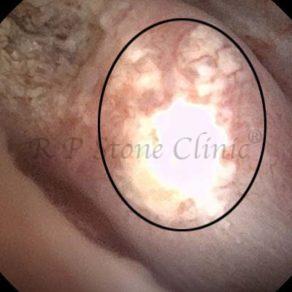

Kidney stone is a solid mass of CRYSTALS. It is the process of crystallization which initiates the formation of kidney stones. This happens in nephrons or units of kidney. Once a small crystal is formed, it can both grow & unite with other crystals leading to the formation of small concretion which eventually forms a stone. Once these large crystals detach from the collecting ducts, the process of stone formation starts in the renal collecting system. A recurrent kidney stone former is advised to know a little bit about something known as Randall’s plaque. Alexander Randall discovered plaques on the renal papillae eight decades back based on examination of 1154 pairs of autopsied Kidneys. He described these renal papillary lesions as cream colored or milk patch areas composed of calcium phosphate & calcium carbonate. These plaques could act as NIDUS for formation of KIDNEY STONE. Calcium Oxalate stone can form on this nidus & then detaches from this plaque to become a free floating stone in the collecting system of kidney

These images are taken as snap shots from the video recording of RIRS Surgery done at our hospital. These are Randall’s Plaques seen with Digital FLEX XC & Digital FLEX XC S. The cream or whitish patches are seen on the tips of RENAL PAPILLAE as seen in images below.

Randall’s Plaques may lead to the formation of Stones.

Those kidney stone patients who have Randall’s Plaques in their kidneys are more likely to form stones again (Recurrent Stones).

Stone Patients in whom Randall’s Plaques are detected at the time of RIRS Surgery should undergo regular ultrasound examination for early detection of stones.

Patients of Stones with Randall’s Plaques in their Kidneys should drink plenty of fluids in addition to Orange Juice & Lemonade.